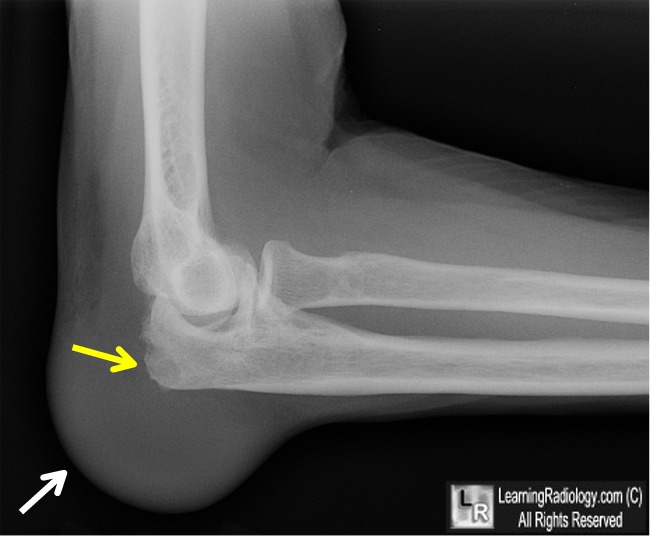

From www.learningradiology.com

LearningRadiology Is Gout In Elbow Painful  Gout in the elbow is a form of arthritis that affects the elbow joint. When your body has extra uric acid, sharp crystals can form in your joints (usually your big toe). With severe gout, even touching the affected joint may be unbearable. Here’s how to know the signs of gout versus other causes of. Gout is a disorder that. Is Gout In Elbow Painful.